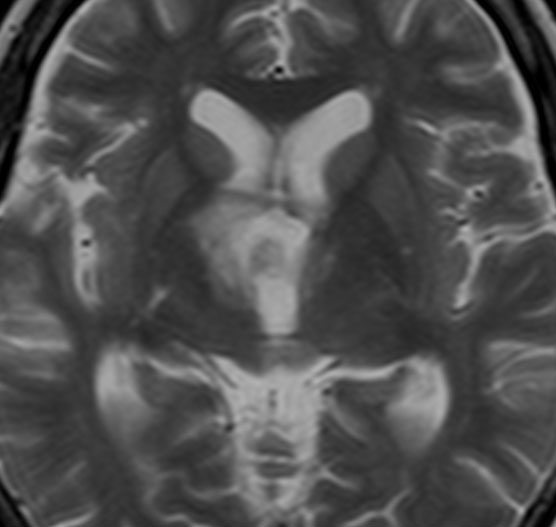

ちょっと大きな頭蓋咽頭腫です

嚢胞(液体が入っている袋)の部分と,腫瘍細胞が固まっている実質部分が入り交じっています。このくらいの大きさになってしまうと,下垂体機能を残すことはとても難しくなります。視神経が圧迫されて視力低下と視野障害を生じます。第3脳室が腫瘍で閉塞していて水頭症になっていますから知能の活動が低下します。

腫瘍を摘出するのに危ないのは,脳の血管の損傷です。左では白く,右では黒く線状に移っているのが太い脳動脈です。これら以外にもたくさんの細い重要な動脈が絡んでいます。

幸いこの患者さんの腫瘍は摘出できて患者さんは元気になりました。でもこのくらいのサイズになると手術がいつもうまくいくとは限りませんし重大な障害が残ることもあります。